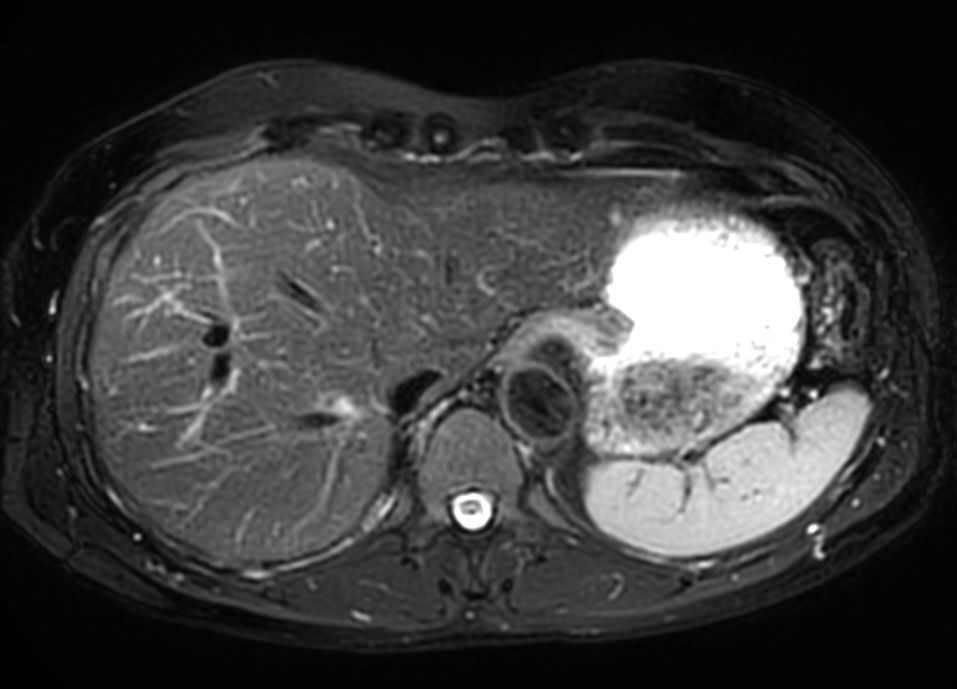

Axial T2w TSE MultiVane XD